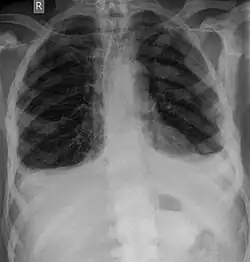

Röntgen

Für die initiale Diagnosestellung hat das konventionelle Röntgenbild eine zentrale Bedeutung. Die Indikation für Aufnahmen in zwei Ebenen ist bei dem Verdacht auf Knochentumoren immer gegeben.[85] Osteolytische Metastasen sind durch eine Abnahme der Knochendichte gekennzeichnet. Dies ist in der Röntgenaufnahme aufgrund der höheren Transparenz für Röntgenstrahlen, durch einen höheren Schwärzungsgrad zu erkennen. Umgekehrt zeigen osteoplastische Metastasen wegen der Zunahme der Knochendichte einen geringeren Schwärzungsgrad. Osteolytische Knochenmetastasen sind an der Wirbelsäule deutlich schwieriger zu erkennen; meist erst dann, wenn bereits etwa 50 % der Gesamtknochenstärke verlorengegangen ist.[85]